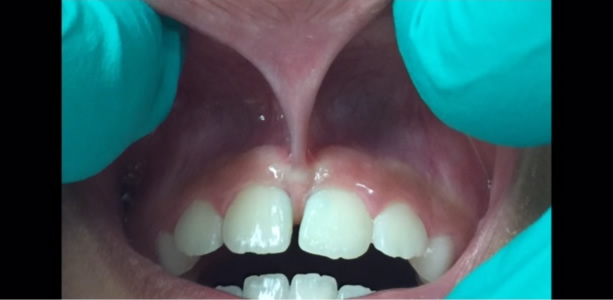

A lip-tie occurs when the upper lip remains attached to the upper gum. Challenges that can occur in children and infants with moderate to severe lip-ties include:

• Formation of a large gap between the maxillary central incisors, called a diastema

• Repeated trauma to the maxillary frenum because it is so low and prominent